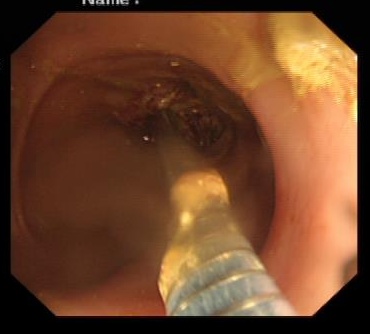

穿越“封锁线”:首先要将一根细长的导丝穿过肿瘤狭窄的缝隙。这需要极大的耐心和手感,患者肿瘤位置扭曲,肠道内粪便和血液堆积,视野极差,处于“看得见摸不着”的地方,陈华不断变换角度和位置,终于让导丝顺利通过。

架设“生命之桥”:在放置支架时,因肿瘤形态导致支架与肠壁形成了一个危险的30度夹角,难以越过狭窄段。此时若强行推进,极易导致肠道穿孔,后果不堪设想。

千钧一发之际,陈华沉着应对,通过反复、轻柔地推拉和调整,不断尝试最佳角度,如同在体内进行一场精密的“穿针引线”。最终,凭借丰富的经验和稳定的手法,支架被精准地放置到了预定位置,肠道瞬间被撑开,“生命通道”恢复了畅通!